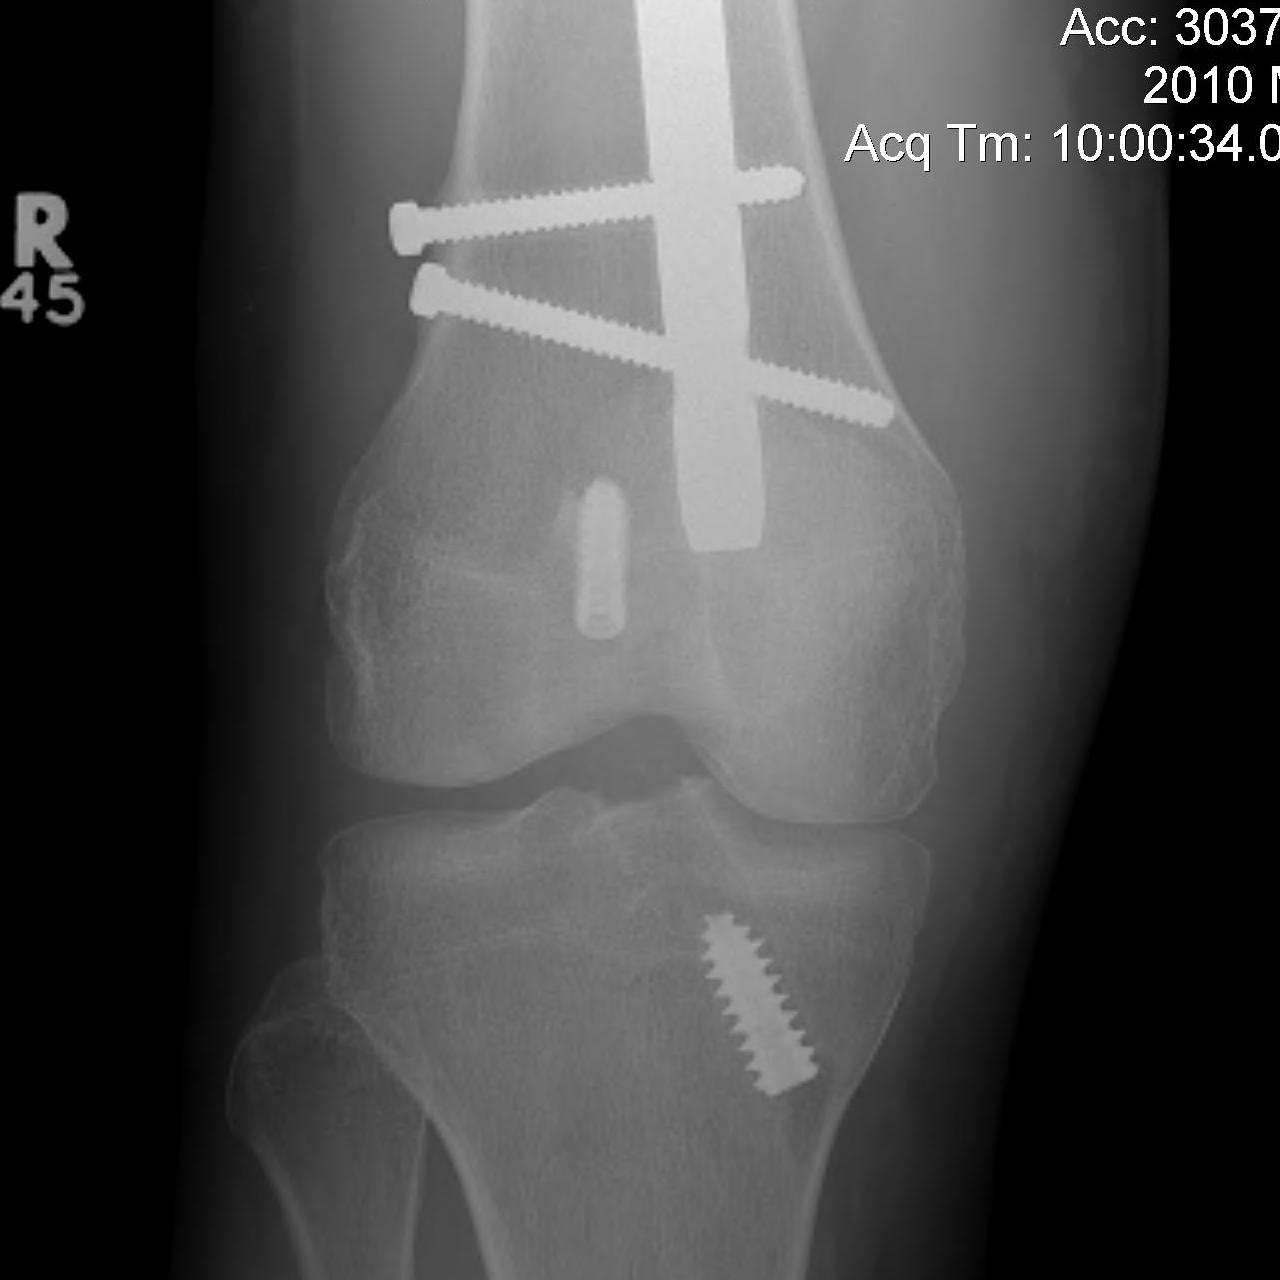

Floating Knee

Ipsilateral femur + tibial fracture

1. Floating Knee

Single incision at knee

- retrograde femoral nail

- tibial IMN if appropriate

High complication rates including non union / malunion, knee stiffness and hetertopic ossification